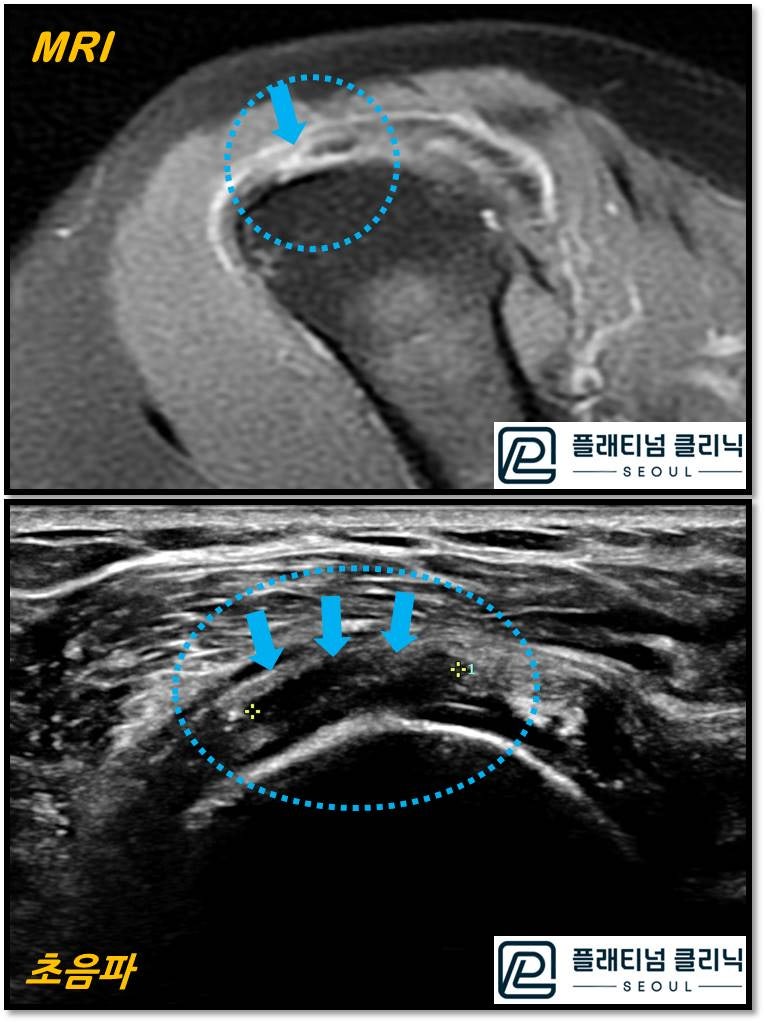

회전근개 파열에서 MRI 와 초음파를 비교한 사진입니다. 위의 사진이 MRI 이며 아래쪽에 있는 것이 초음파 사진입니다. 노란 원안에 화살표로 표시된 부위가 파열된 부위인데 MRI 에서는 힘줄이 검게 보이고 파열된 부위가 하얗게 보입니다. 초음파에서는 힘줄이 하얗게 보이고 파열된 부위가 검게 보입니다. 어떻게 보이시나요? 저는 초음파가 더 선명하고 크게 보입니다. 실제로 힘줄의 실질도 잘 관찰이 되고 근육이 방향도 잘 관찰됩니다. 물론 초음파를 오랜기간 봐 왔기 때문에 어느정도 숙련도가 있어서 더 잘보이는 것도 있을 겁니다.